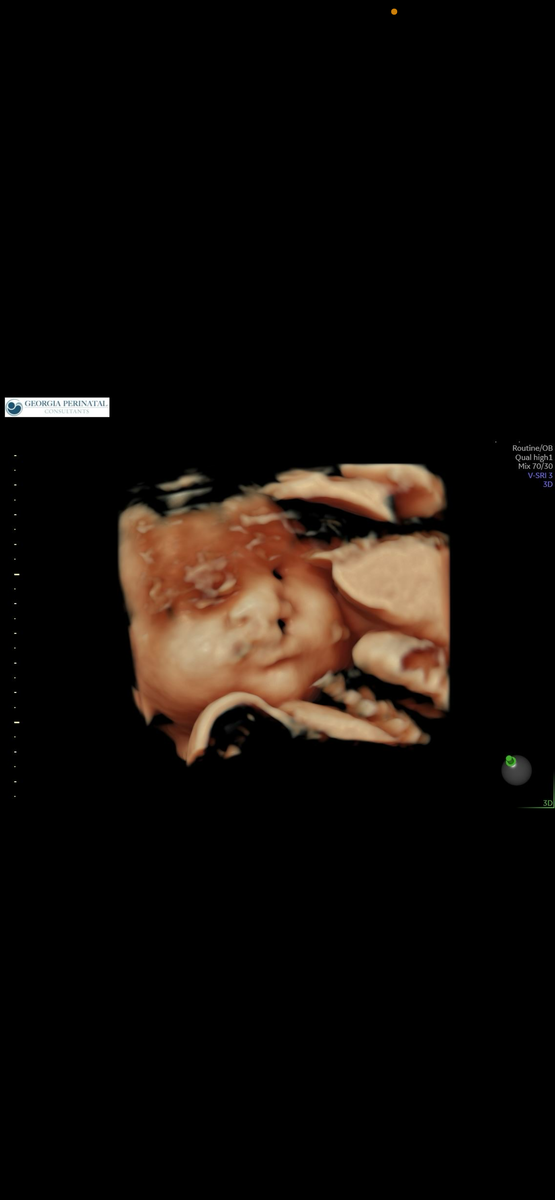

Всем доброго времени суток! Меня зовут Алена, я мама счастливого ребенка с расщелиной губы и неба. Сын родился в США в мае 2024. На момент написания статьи нам всего два месяца. Часть 1. С чего все началось. Итак, это мой третий ребенок. Мне 39 лет, мужа 45. Беременность протекала обычно, без осложнений . Хотелось спать, болела спина - но это мелочи конкретно моего организма . Никаких гестозов, других патологических состояний у меня выявлено не было . Наблюдалась тут же в США всю беременность. Проходила плановые осмотры, визиты, сдавала анализы. Так как я старше 35 лет то сдавала кровь на генетику NIPD аналог panorama test, выявляет самые распространенные синдромы (дауна, Патау и др.) все было отрицательным. Этот же тест определил пол ребенка. Как объяснил мне мой врач такой тест не дает ложно отрицательный результат . Нет значит нет. Я спала спокойно. Вплоть до второго УЗИ на 20 недели ничего не беспокоило. В декабре 2023 было плановое УЗИ 20 неделя. Узист внимательно фиксиро